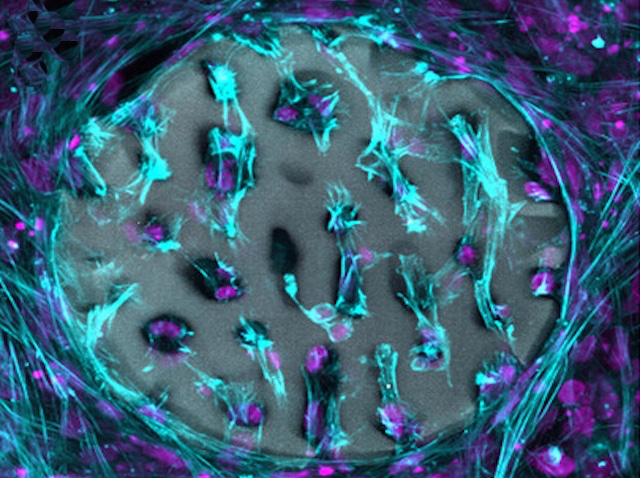

Les característiques que definixen les cèl·lules mare són la seua capacitat de convertir-se en diversos tipus cel·lulars i la seua habilitat per a autorenovar-se. Aquesta capacitat d’autorenovació garantix el manteniment de les reserves de cèl·lules mare en el cos i, si els científics saben aprofitar-la bé, també al laboratori. Quan es mantenen cultius de cèl·lules mare al laboratori, els investigadors solen utilitzar diferents combinacions de factors específics per a cada tipus de cèl·lula mare. No obstant això, investigacions recents han identificat un punt de control comú (la quinasa reguladora GSK3), que, quan s’inhibix, manté la capacitat d’autorenovació en diversos tipus de cèl·lules mare i en diferents espècies. De fet, la inhibició de GSK3 ha permés cultivar conjuntament epiblasts de ratolí i cèl·lules mare embrionàries, com es mostra a la imatge (en verd i roig), mantenint alhora les seues identitats pròpies, cosa que fins ara era impossible. A més de millorar les tècniques de cultiu de cèl·lules mare, el descobriment d’aquest punt de control comú podria tindre aplicacions clíniques per a millorar la salut i la regeneració de teixits envellits.

Imatge de Duo Wang/Ying Lab/USC Stem Cell. Publicació de Duo Wang i Xiukun Wang, i col·laboradors/es

Eli and Edythe Broad Center for Regenerative Medicine and Stem Cell Research at USC, Keck School of Medicine, USC, Los Angeles, CA; Epigenetics and RNA Biology Laboratory, National Institute of Environmental Health Sciences, Durham, NC, EUA

Publicat en Cell Research, abril de 2026